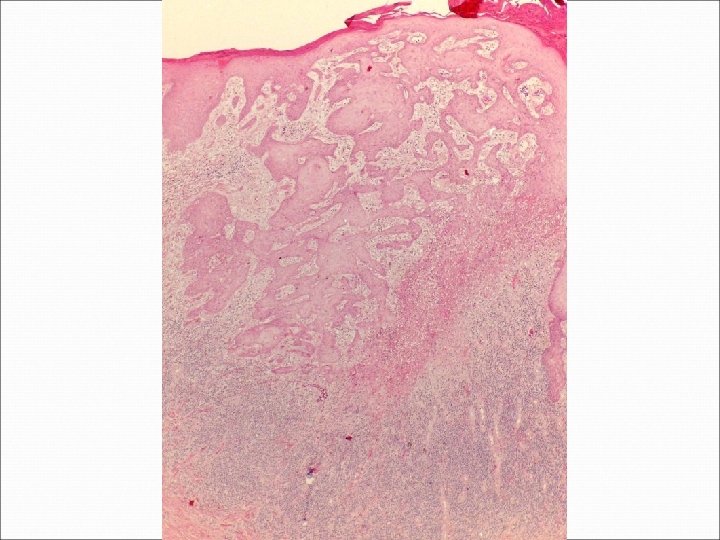

�Case number: 185 �Clinical: Male aged 70 years. ? BCC �Immuno: Pancytokeratin shows strong

�Case number: 185 �Clinical: Male aged 70 years. ? BCC �Immuno: Pancytokeratin shows strong positivity in centre of lymphoid islands. EBV negative.

Most popular diagnosis � Lymphoepithelioma-like carcinoma